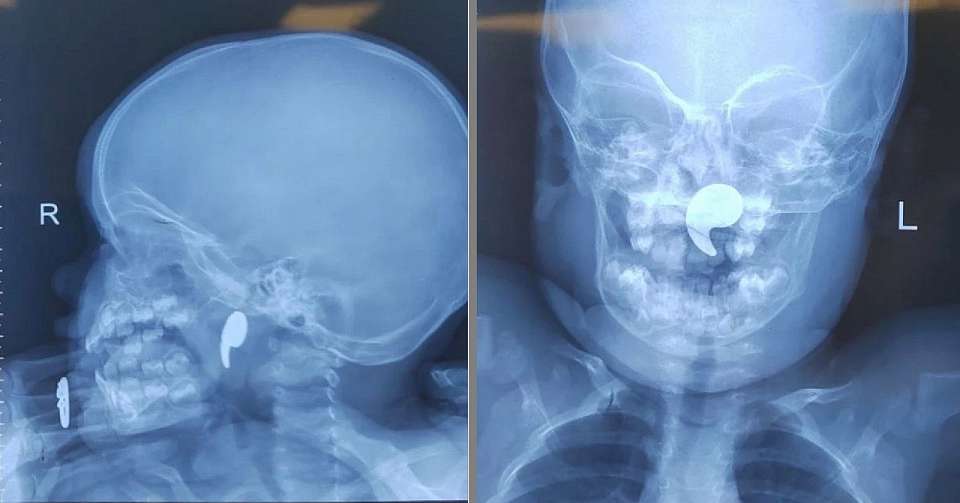

По словам родителей, малышка играла магнитом в форме запятой. Мать попыталась самостоятельно извлечь инородный предмет из носа дочки, однако тот сместился в носоглотку.

Дежурный ЛОР-врач Марина Перепечена провела операцию под общей анестезией с использованием эндоскопического оборудования. Магнит в итоге был успешно извлечён. Через сутки состояние девочки стабилизировалось, и она была выписана под наблюдение педиатра.